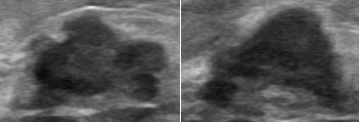

Is the model paying attention to the same attributes as radiologists when predicting whether a lesion is malignant? To gain insight about this question, we applied the Grad-CAM algorithm [26] to our best trained GoogleNet. Grad-CAM produces a gradient-based heat-map that highlights input parts that most influenced the output prediction.

In Figure 8, we present several mammography and ultrasound malignant examples from the training set, with their Grad-CAM computations. “Hotter” areas indicate attended regions. We observe that for malignant lesions, the model appears to rely significantly (hot colors in heat map) on the lesion boundaries, especially where irregular features are encountered, in agreement with the radiologist diagnostic methodology.

Refer to caption

Figure 8: Examples of malignant lesions from the training set with their Grad-CAM visualizations (Top-mammography, Bottom-ultrasound).